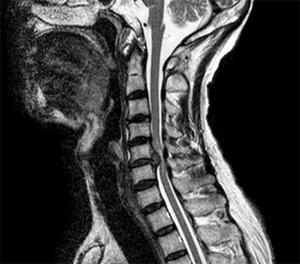

56歳の男性。数年前から頸椎椎間板ヘルニアを指摘されていた。昨日、自宅で転倒して突然に麻痺を呈した。頸髄損傷と診断され、主な損傷部位以下の機能はASIA機能障害尺度でBである。頸椎MRIを示す。正しいのはどれか。

H1SMaGjVRCnKM34ngZR2O